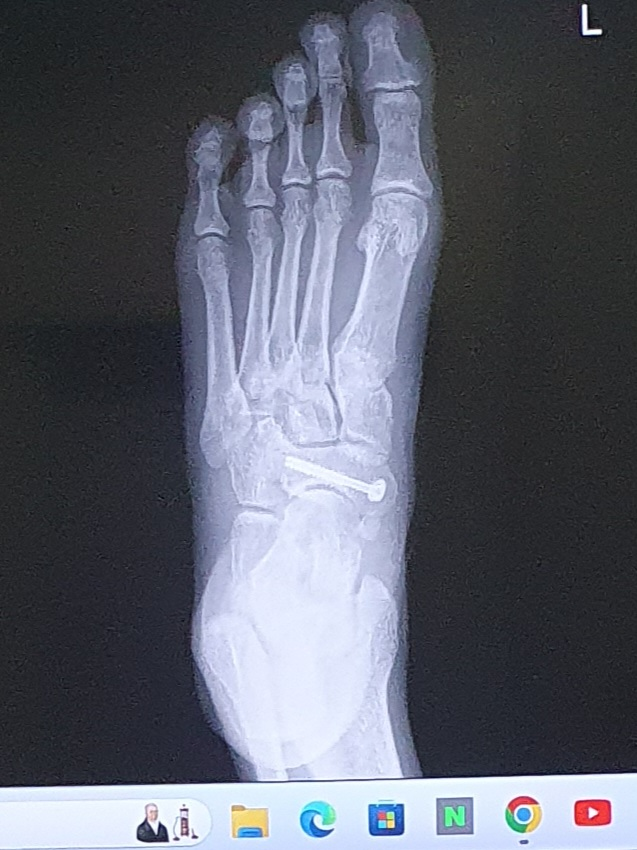

발등 골절수술을 받고 엑스레이를 찍었는데 위치가 이렇게 바뀔수있나요?

5일 입원하고 퇴원 후 1주일 간격으로 x-ray찍은건데

철심이 좀 더 발등뼈쪽으로 이동한게 보여집니다

• 2번 째 사진

촬영된 각도가 조금 차이가 나서 다르게 보이는 것이지 실제로 핀이 움직이지는 않았을 것이라 보입니다. 3차원 구조물을 2차원 평면에서 관찰하는 사진이므로 매번 완벽히 동일한 사진이 촬영되기는 어렵습니다.

찍는 각도에 따라 변화가 있는 것으로 보이며 철심히 더 깊이 박혔다던가 이동했을 것으로 보이지는 않습니다.